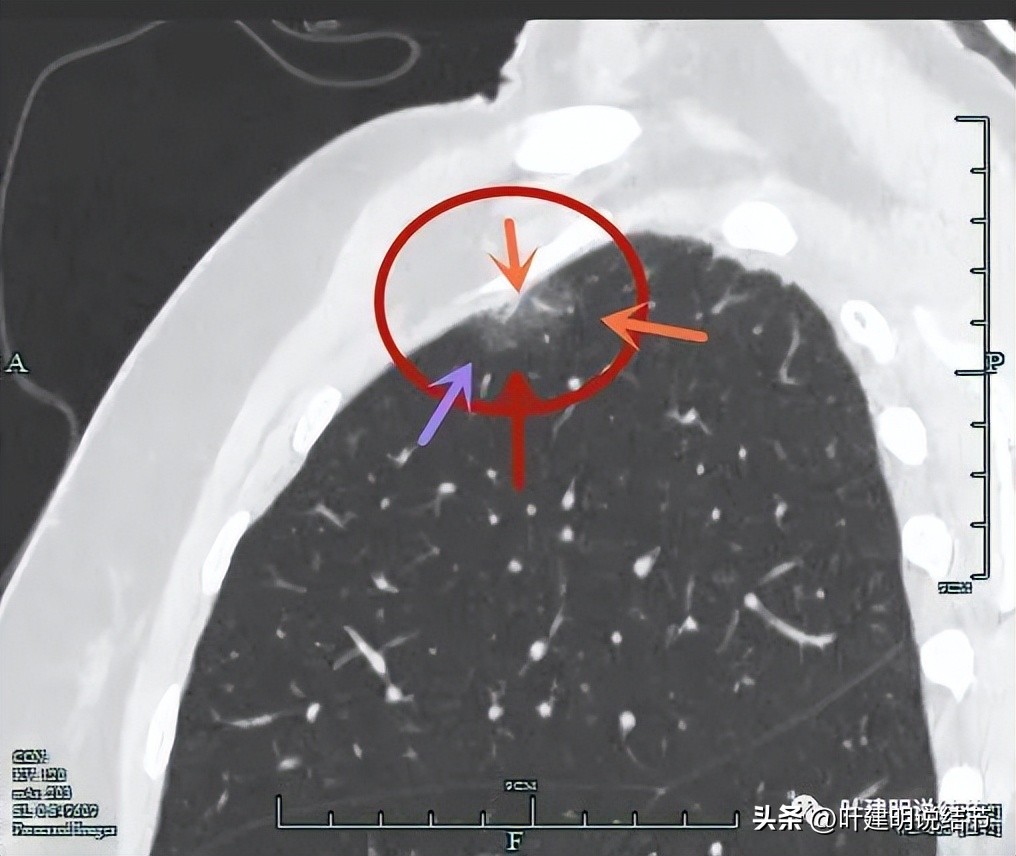

靶扫描上图层面见病灶内部有实性成分,与胸壁间没有间隙(蓝色箭头),灶内有血管穿行(桔色箭头),整体轮廓清(红色箭头)。

实性部分密度不均,散在,杂乱(粉色箭头),有明显血管发出分支进入病灶(桔色箭头)。

灶内血管穿行、边缘不平有毛刺、整体轮廓清。

血管进入,间隙消失、轮廓清

上图也非常典型,几乎集齐它该有影像特征:灶内实性成分(粉色箭头);与胸壁间间隙消失(蓝色箭头);整体轮廓与瘤肺边界清(红色箭头);灶内血管穿行以及小血管进入(桔色箭头);表面不平有分叶(砖色箭头);边缘有毛刺征(紫色箭头)。